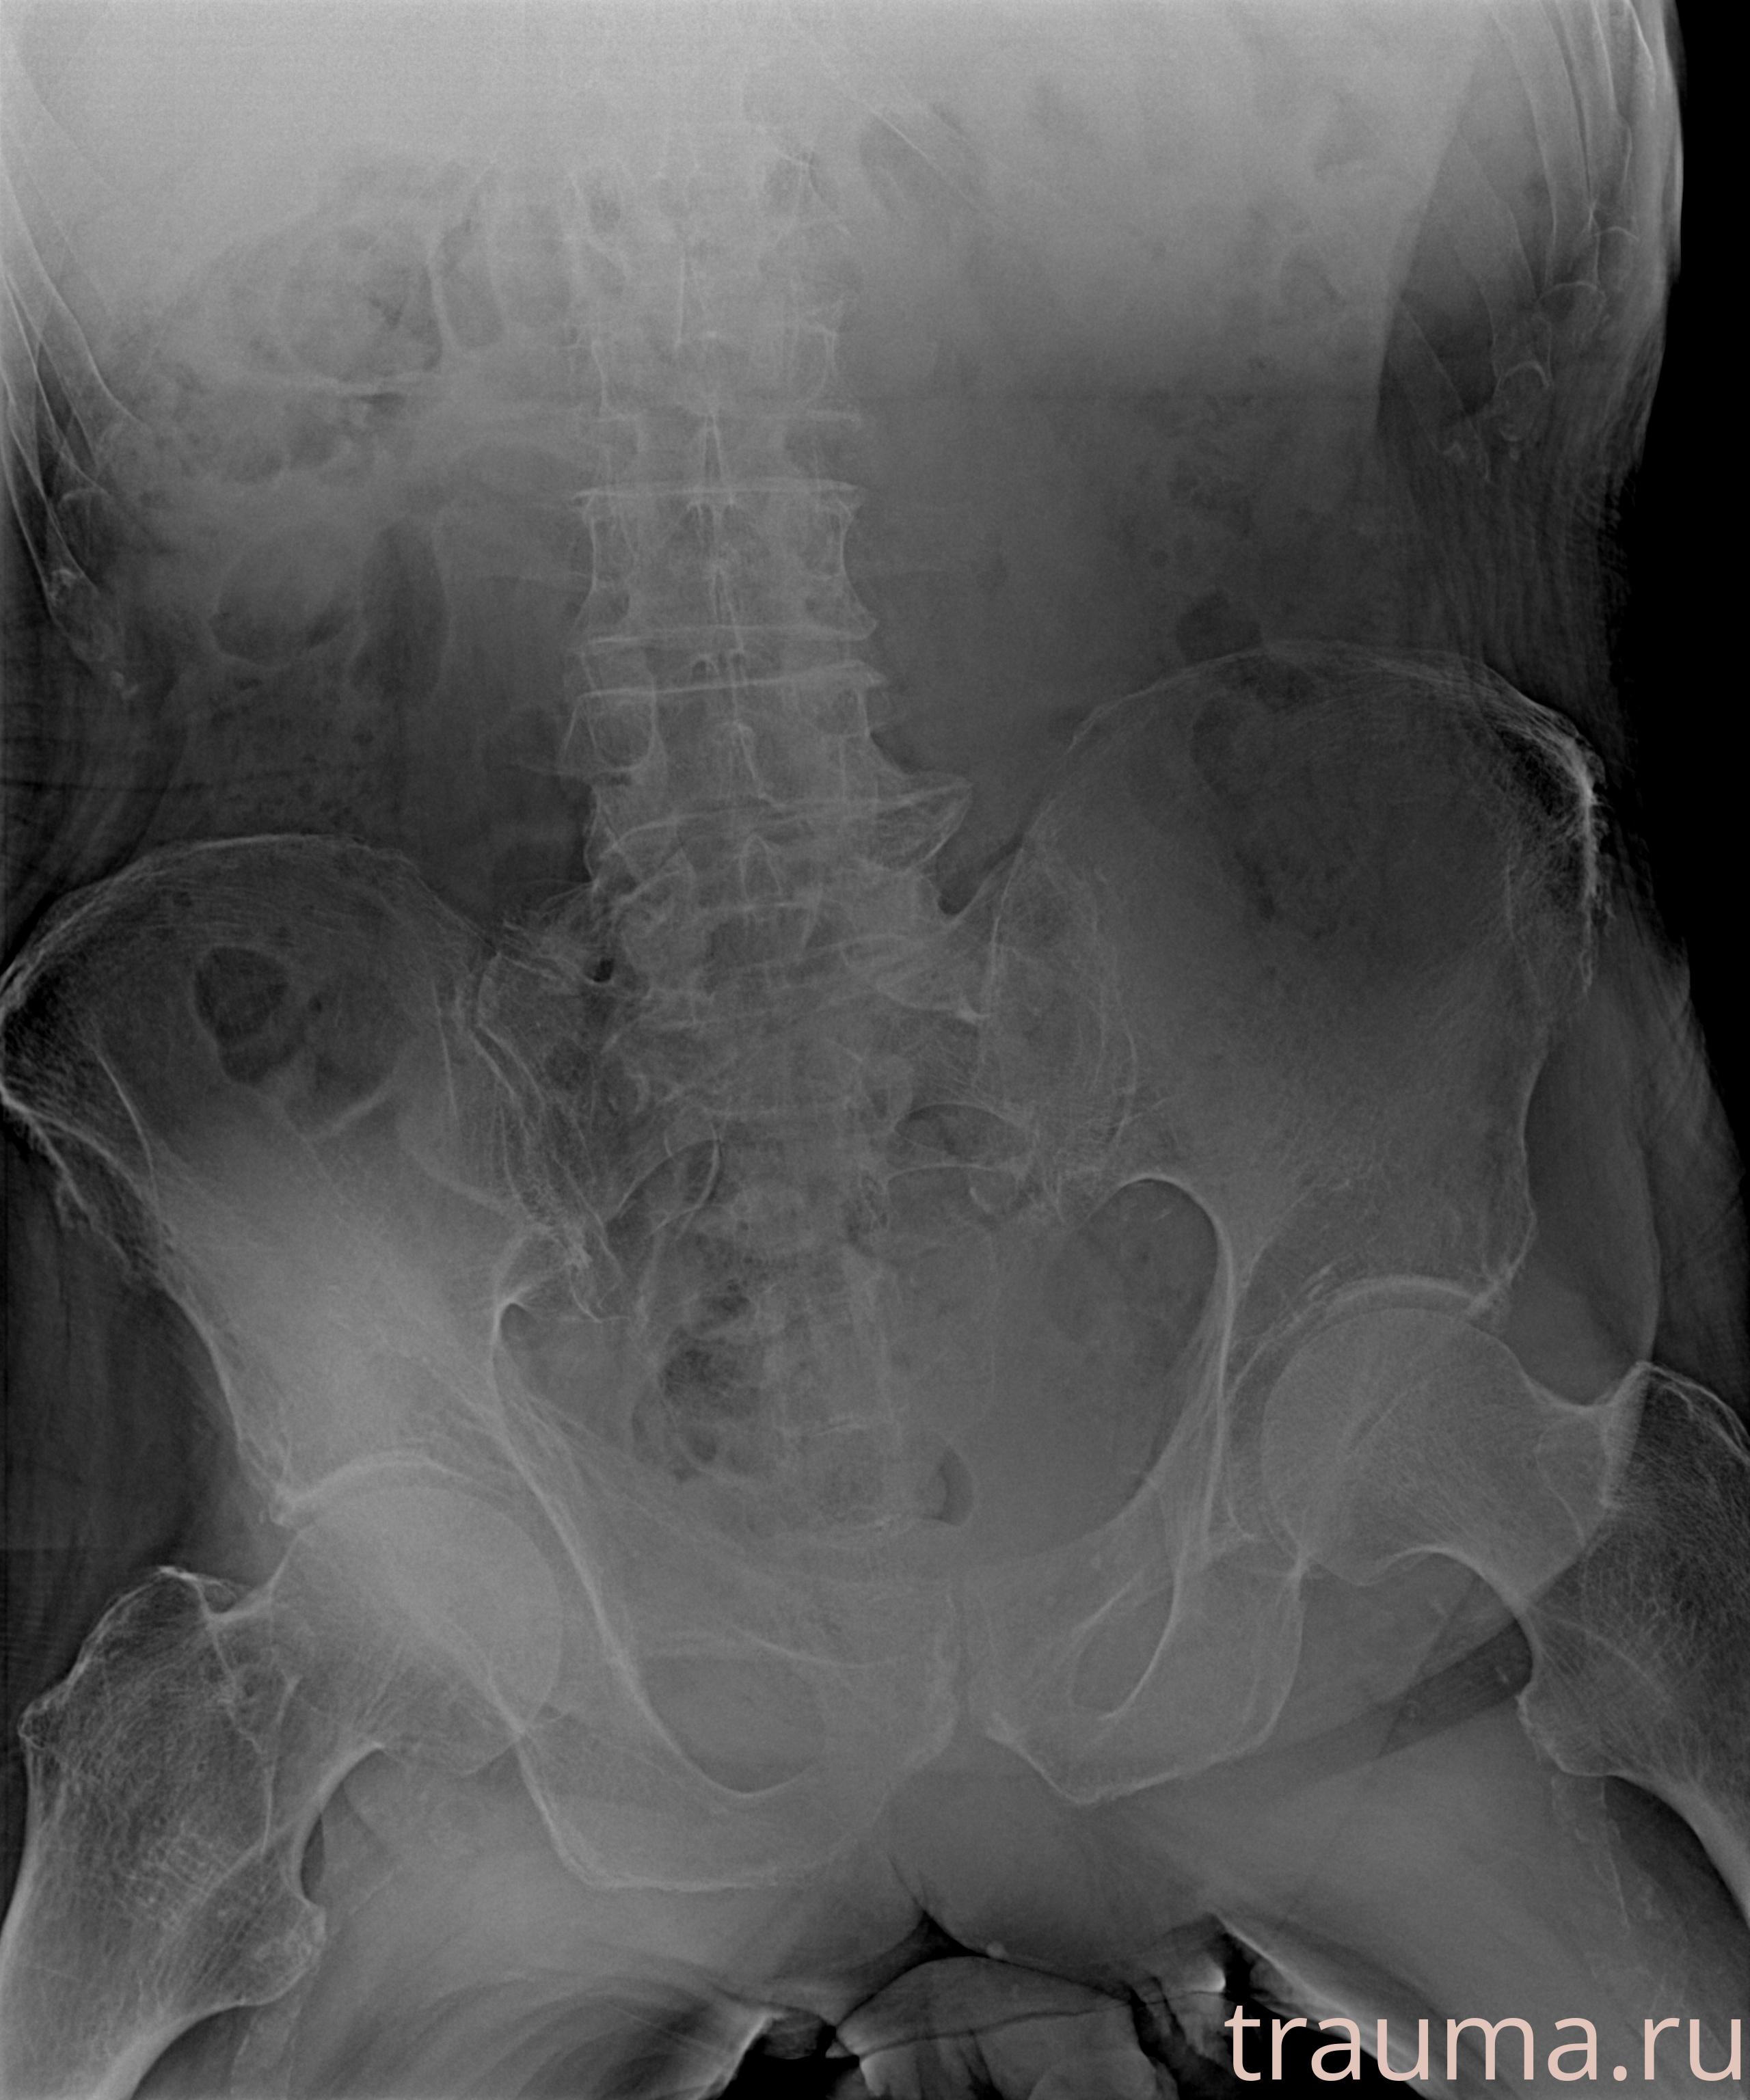

Рентгенограммы

Рентген на дому: по вашему адресу приезжает врач-рентгенолог, травматолог-ортопед с мобильным рентгеновским аппаратом, проводит диагностику травмы или заболевания, делает необходимые рентгенограммы, дает рекомендации по дальнейшему лечению. Получить качественные снимки в домашних условиях возможно благодаря уникальной методике, разработанной МосРентген Центром для института  Склифосовского